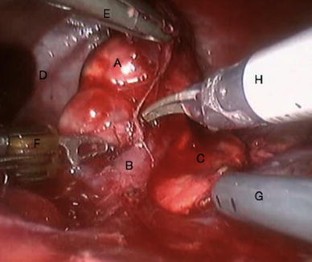

Mini-invasive surgery is more and more integrated in pediatric surgery. The robotic-assisted surgery brought new advantages from which the patient and the surgeon could benefit compared to laparoscopy. Its use in oncological surgery is still controversial. 12 robotic-assisted tumor resections with the da Vinci Surgical Robot (Intuitive Surgical, Sunnyvale, CA) were attempted in 11 children (mean age 7.65 years; age range 0.75–16.75 years; mean weight 30.3 kg; weight range 8.6–62 kg) in two centers. Mean total operative time was 145 min (range 72–263 min). 1 procedure (8.3%) was converted. The pathology included renal tumors (n = 2; one nephroblastoma, one metanephric adenoma), adrenal tumors (n = 9; three neuroblastomas, two pheochromocytomas, two adrenocortical adenomas, one cystic lymphangioma, one paraganglioma) and a pancreatic tumor (n = 1; one pancreatic cyst). 4 tumors (33.3%) were malignant. Every patient underwent a R0 resection. 1 child (8.3%) developed a post operative complication. Mean length of hospitalization was 3.0 days (range 2–5 days). Followup averaged 3.3 years with no recurrence. All children are alive. Robot-assisted MIS seems to be safe and feasible in pediatric tumors. The oncological surgical principles were respected in our series with low morbi/mortality and good long-term results. Robotic surgery and its technical advantages bring potential benefits for children with cancer. It has a role to play in pediatric oncological surgery but its place and indications still need to be better defined.